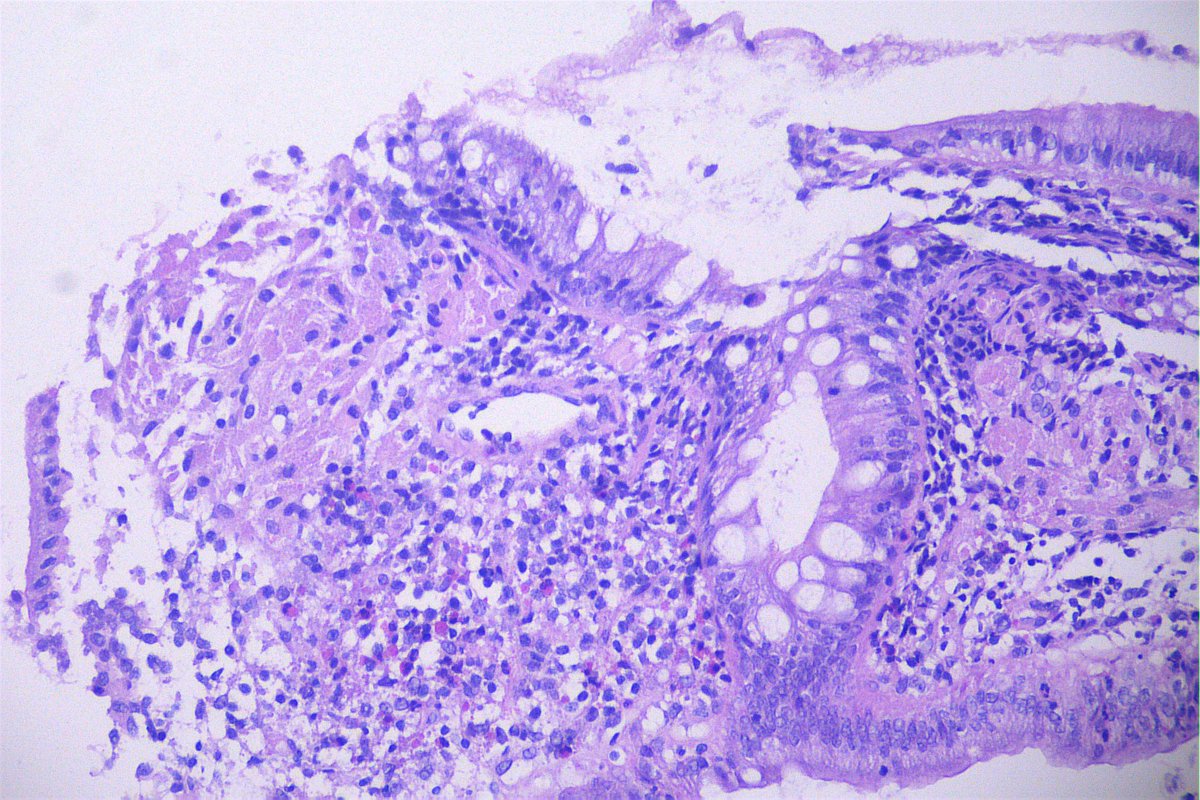

Case of the day. M, 30 years old, with weight loss, pulmonary consolidation area, mediastinal lymph node enlargement, and endobronchial polypoid lesions. Bronchial biopsy performed. #pulmpath #pathology